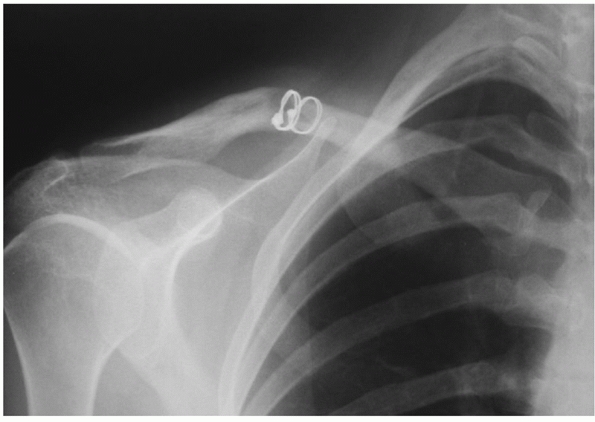

AP radiographs. Centering the radiograph on the acromioclavicular joint

and angling the beam in a cephalic tilt of approximately 15 degrees

(the Zanca view) helps delineate the fracture well, by removing the

overlap of the upper portion of the thoracic cage.29,30

To accurately delineate the degree of fracture displacement, these

radiographs should be taken with the patient standing and the arm

unsupported by slings, braces, or the uninjured arm. On occasion, it

may be useful to obtain a stress view to determine the integrity of the

coracoclavicular ligaments (as this can influence the choice of

fixation): a 5- to 10-pound weight is suspended from the wrist of the

affected arm and then radiographs

are

taken. CT scanning of lateral clavicle fractures is rarely required

clinically but can be useful in selected cases to determine

intra-articular extension or displacement.